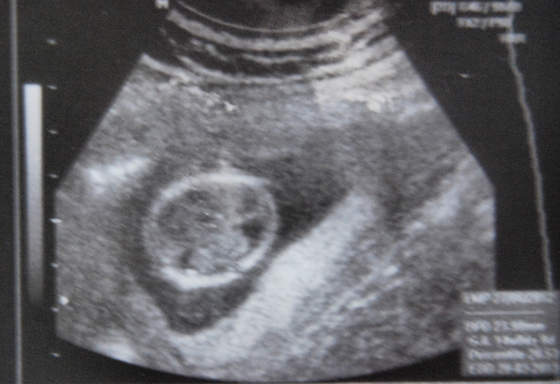

) więc teraz nawet nie zapytałam o 3D/4d (Cytruskiku- zdjęcie to 3D a 4D widziałam na żywo i na filmiku jak małe się rusza :-)) a tu przemiła młoda pani dr (Anna Totko) sama włączyła 3D i pokazała nam takie oto moje "cudo"